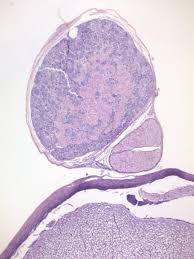

The subdivisions of the autonomic nervous system.

Enteric Nervous System. DIVISIONS OF THE AUTONOMIC NERVOUS SYSTEM SYMPATHETIC DIVISION PATHWAYS. Which division of the autonomic nervous system is illustrated by the purple neurons. The most common are norepinephrine NE and acetylcholine Ach. The autonomic nervous system releases chemical messengers to influence its target organs. Sympathetic and parasympathetic fibers Which type of nerve fibers make up the autonomic nervous system ANS. Alternate name for the parasympathetic division of the autonomic nervous system that is based on the anatomical location of central neurons in brain-stem nuclei and the lateral horn of the sacral spinal cord.